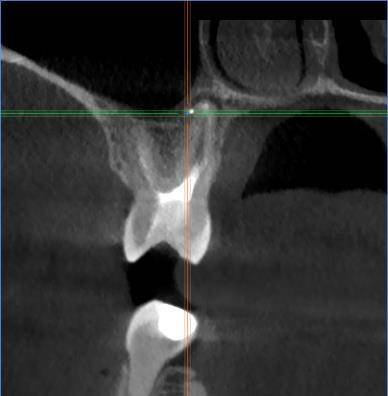

Есть зуб 11 (с СВШ) с восспалением около корня. До брекетов тоже было.

Перед протезированием предлагают перелечить каналы через корень с извлечением СВШ и последующим восстановлением (не понятно правда с СВШ или уже без него. Без СВШ зуб прям под корень может обломаться) под коронку.

До этого предлагали резекцию. Как в итоге лучше, через корень или резекцию?11-2.jpg.ba542aa82cfd6ddaad3fb9e234b99d99.jpg11.jpg.a34f40916e8e638d622001c50fff6e3a.jpg11-3.jpg.7a281f5893f8e6440937071fda10d523.jpg11-4.jpg.6a62c56e00cfdfa00cf35b7e276fd908.jpg